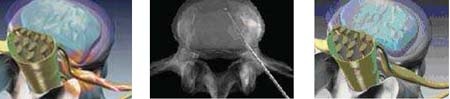

Nucleoplasty là phương pháp phẫu thuật nội soi xâm lấn tối thiểu cho bệnh nhân thoát vị đĩa đệm được phát minh năm 2000, sử dụng công nghệ tia plasma duy nhất được gọi Coblation ® loại bỏ các mô từ trung tâm đĩa đệm. Phương pháp mới này đã được thực hiện tại Singapore để điều trị đau lưng và đau thần kinh tọa kể từ năm 2005 và Khoa Chấn Thương Chỉnh Hình Bệnh Viện Raffles là trung tâm đầu tiên áp dụng phương pháp này điều trị cho bệnh nhân bị đau cổ, lưng.

Dưới sự hỗ trợ của máy nội soi, một cây kim nhỏ sẽ được đưa vào trung tâm đĩa như một thiết bị Coblation. Thiết bị này sử dụng tần số vô tuyến năng lượng để làm mềm đĩa đệm và loại bỏ đĩa phần đĩa đệm bị chèn ép, giải phóng thần kinh 2 bên, đồng thời đóng vết thương nội đĩa. Khi áp lực nội đĩa giảm, cơn đau sẽ giảm. Phương pháp này tiến hành qua một lỗ kim nhỏ mà không cần phải rạch một vết rạch lớn như phẫu thuật truyền thống. Phương pháp này giúp ích cho bệnh nhân với chèn ép lên rễ thần kinh do thoát vị đĩa đệm nhẹ.